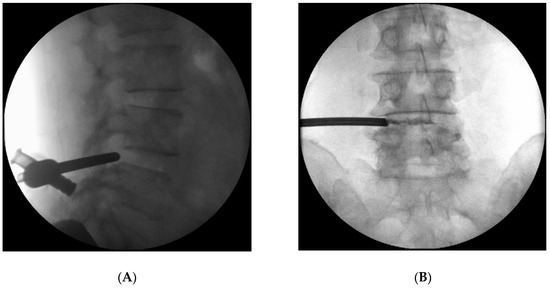

Background and Objectives: The term “Juxtafacet cyst” refers to both synovial cysts and ganglion pseudocysts associated with the lumbar facet joint. As conservative treatment for the juxtafacet cyst has a minimal effect, complete excision through surgery is considered the first choice of treatment. [...] Read more.

Background and Objectives: The term “Juxtafacet cyst” refers to both synovial cysts and ganglion pseudocysts associated with the lumbar facet joint. As conservative treatment for the juxtafacet cyst has a minimal effect, complete excision through surgery is considered the first choice of treatment. In this study, we retrospectively reviewed the clinical outcomes of percutaneous epidural neuroplasty for symptomatic lumbar juxtafacet cysts. Materials and Methods: We conducted a retrospective review of 34 patients with symptomatic juxtafacet cysts who visited a single institute from January 2010 to September 2023. Patients who received conservative treatment for at least 6 weeks but experienced no or insufficient effects were eligible for this study. After neuroplasty, a medical history check and neurological examination were performed during follow-up at 2 weeks, 1 month, 2 months, 3 months, 6 months, and once a year thereafter. Results: The pain improved for all patients to a VAS score of 3 or less immediately after neuroplasty; however, four of those patients (11%) had pain that worsened eventually to the same level as before the procedure and required surgery. The results showed that, regardless of cyst size, in cases with severe stenosis of the spinal canal, the outcome of neuroplasty was poor and often eventually required surgery. The cyst size was not associated with the procedure results. In addition, if the cyst was present at the L4–L5 level, or if diabetes mellitus was present, the likelihood of future surgery was significant (p-value = 0.003). Conclusions: Percutaneous neuroplasty showed a better success rate than other non-surgical treatments. In addition, severe spinal stenosis (Schizas grade C or higher), L4–L5 level, or diabetes mellitus produced a high possibility of surgery due to recurrence. Full article